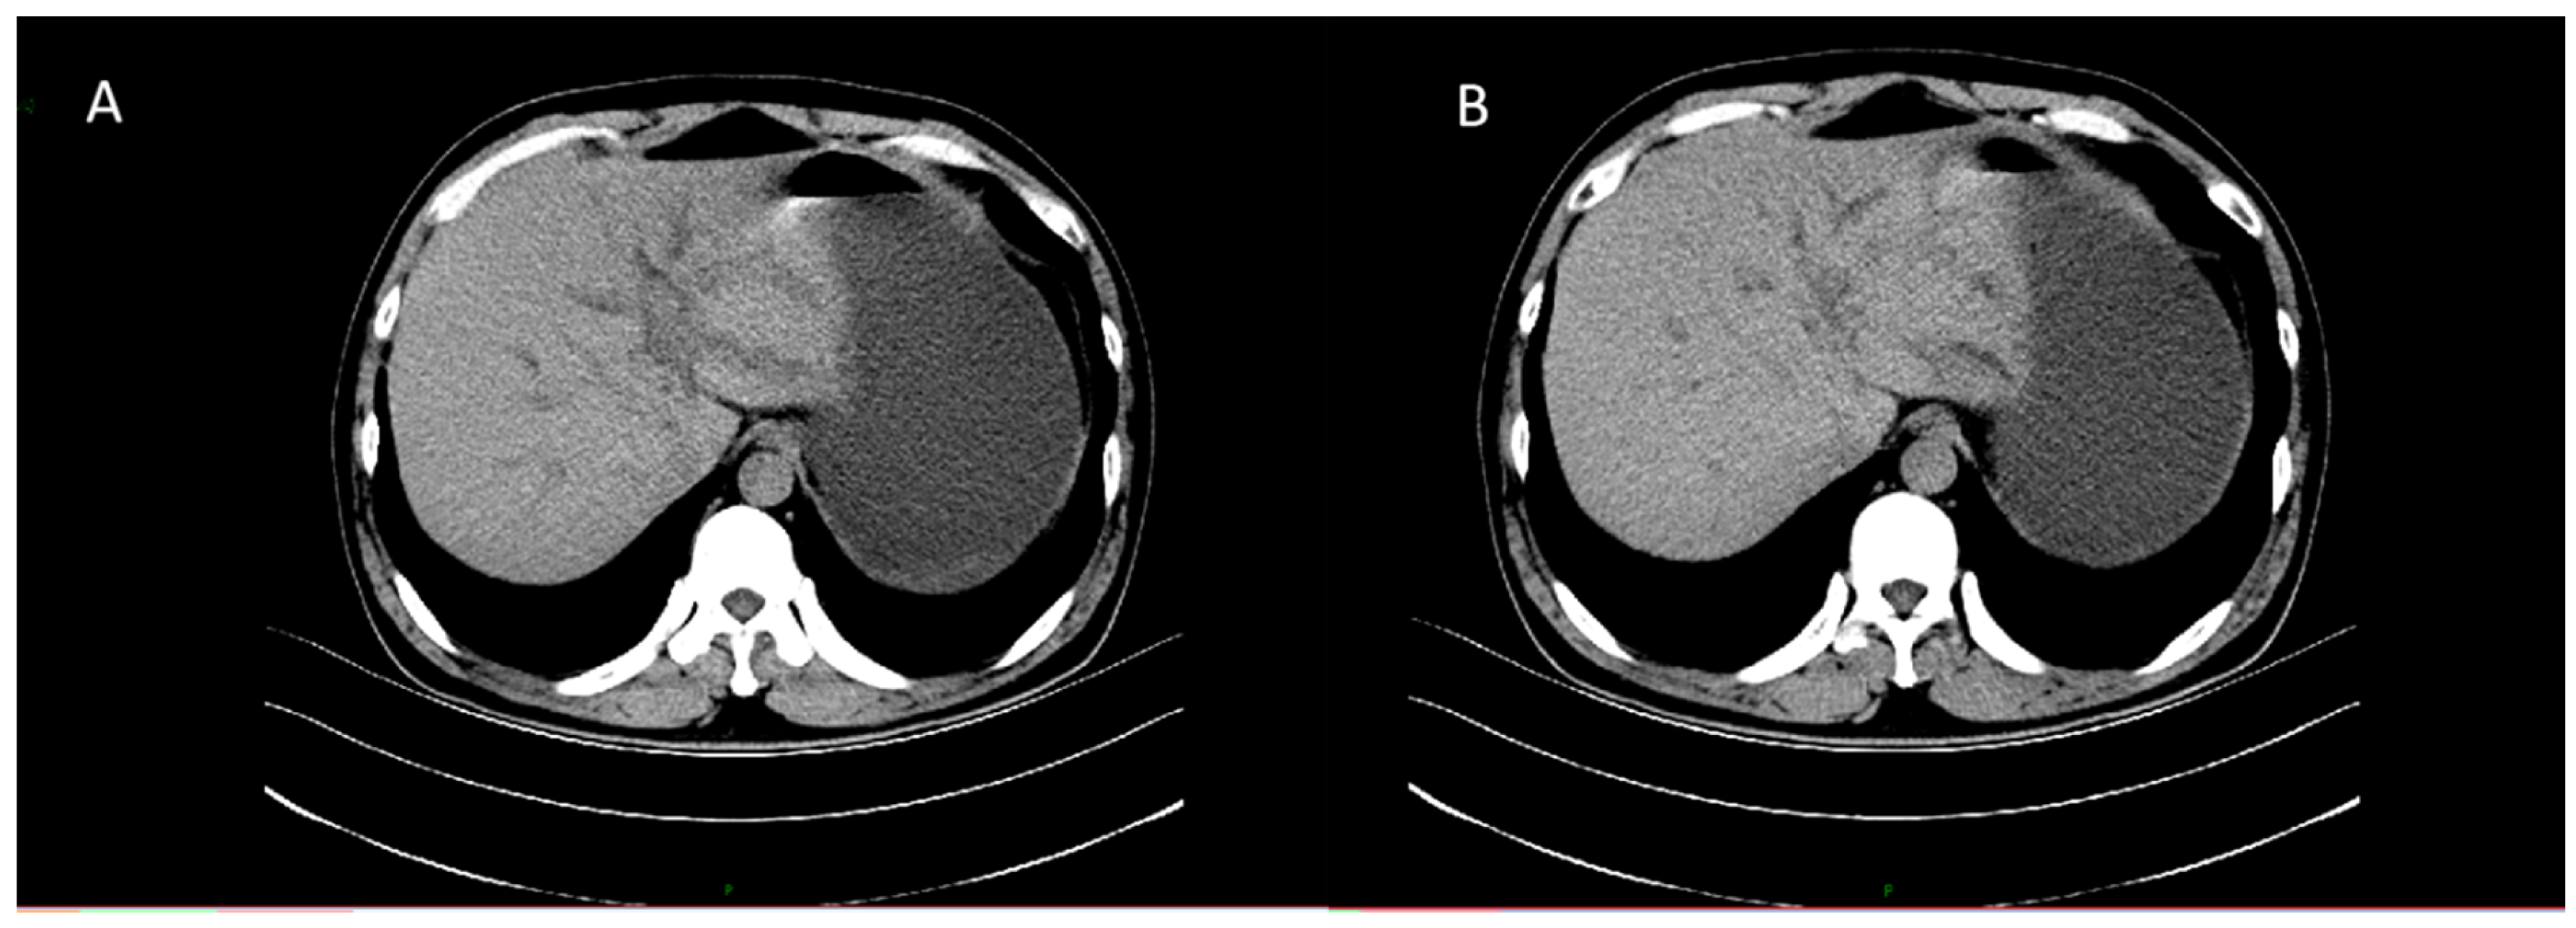

CT revealed patchy low-density lesions in the left hepatic lobe and hilar region, with mild intrahepatic bile duct dilatation and local bile duct wall thickening. The largest lesion was about 14 mm in diameter. Multiple enlarged lymph nodes were seen in the hepatic hilum and hepatoduodenal ligament areas. Malignancy, such as cholangiocarcinoma, was suspected (Figure 1).

Figure 1. Axial contrast-enhanced CT images of the liver. (A) Plain scan shows a patchy low-density lesion in the left lobe of the liver near the hepatic hilum. (B) Arterial phase shows mild heterogeneous enhancement of the lesion.